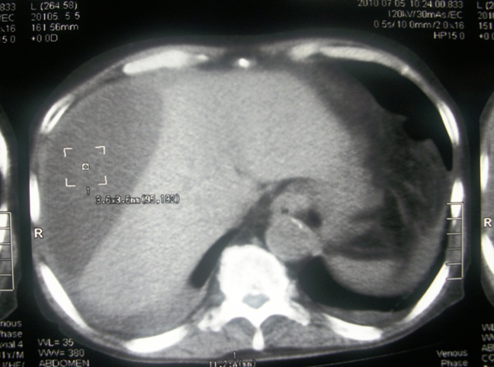

2. Colecciones por complicaciones postquirúrgica, fístulas

Ilustración 3 Tomografía con imágenes de colección liquida días después de apendicetomía

Fuente: Hospital de Especialidades Guayaquil “Doctor Abel Gilbert Pontón”.

Autor: Dr. Fernando Moncayo A.